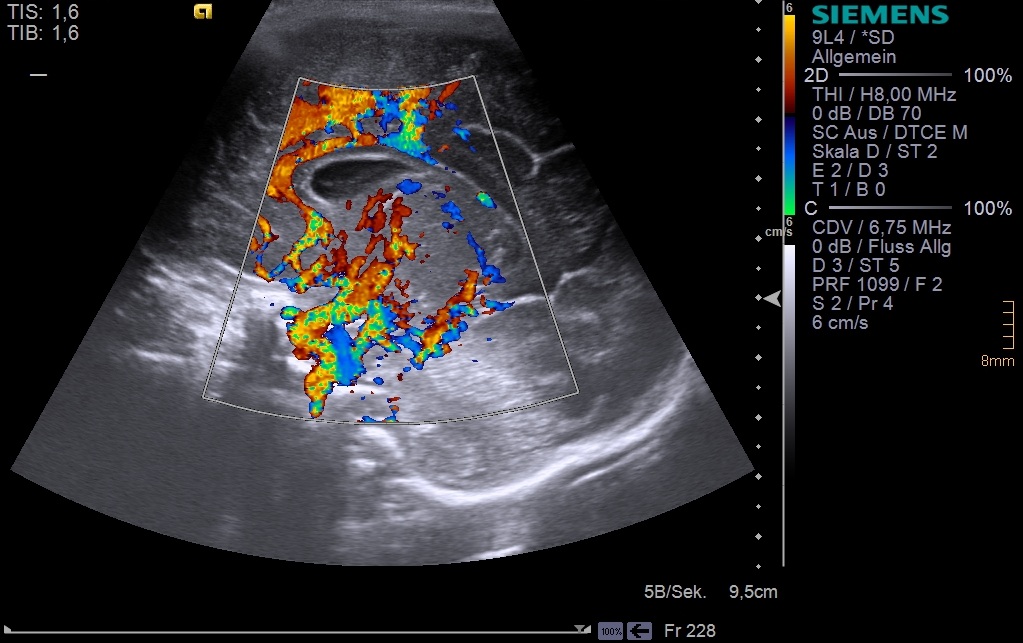

Ultraschall

Sehr viele klinische Fragen können mit einer Ultraschalluntersuchung beantwortet werden. Deswegen ist sie die häufigste und oft auch die einzige bildgebende Untersuchung. Technisch wird das Ultraschallbild mit Hilfe von Schallwellen oberhalb des hörbaren Bereiches erzeugt. Typische Einsatzbereiche sind Bauchschmerzen, Entzündungen der Nieren und Blase, Entwicklungsstörungen der Hüfte (Hüftdysplasie), und der Ausschluss von Hirnblutung bei Früh- und Neugeborenen.

Farbdoppler der hirnversorgenden Gefäße